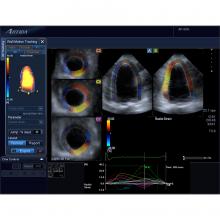

Cardio-oncology is an emerging field that combines the expertise of both cardiology and oncology to assess and treat cancer patients for the second leading cause of death among cancer survivors — cardiovascular disease brought on by their treatments. Specific types of chemotherapy and chest-directed radiation therapy are known to cause cardiac dysfunction, mainly due to cardiotoxicity — the symptoms of which may not present until months or even years after cancer treatment.